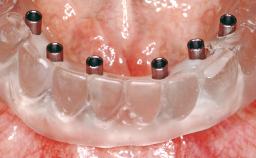

A 35-year-old Caucasian female presenting with advanced periodontal disease involving both the maxillary and the mandibular dentition was referred for evaluation. The patient, a non-smoker in good general health, requested treatment for recurrent periodontal abscesses, tooth mobility, and discomfort during chewing, as well as restoration of her missing teeth with a fixed prosthesis to improve mastication and esthetics. All residual maxillary teeth exhibited plaque deposits, deep pockets, bleeding on probing, and class III mobility and were evaluated as hopeless. All residual mandibular teeth except tooth 37 could be maintained after periodontal therapy.

| # of Implants | 8 |

| Abutment Type | Standard |

| Prosthesis Type | FDP |